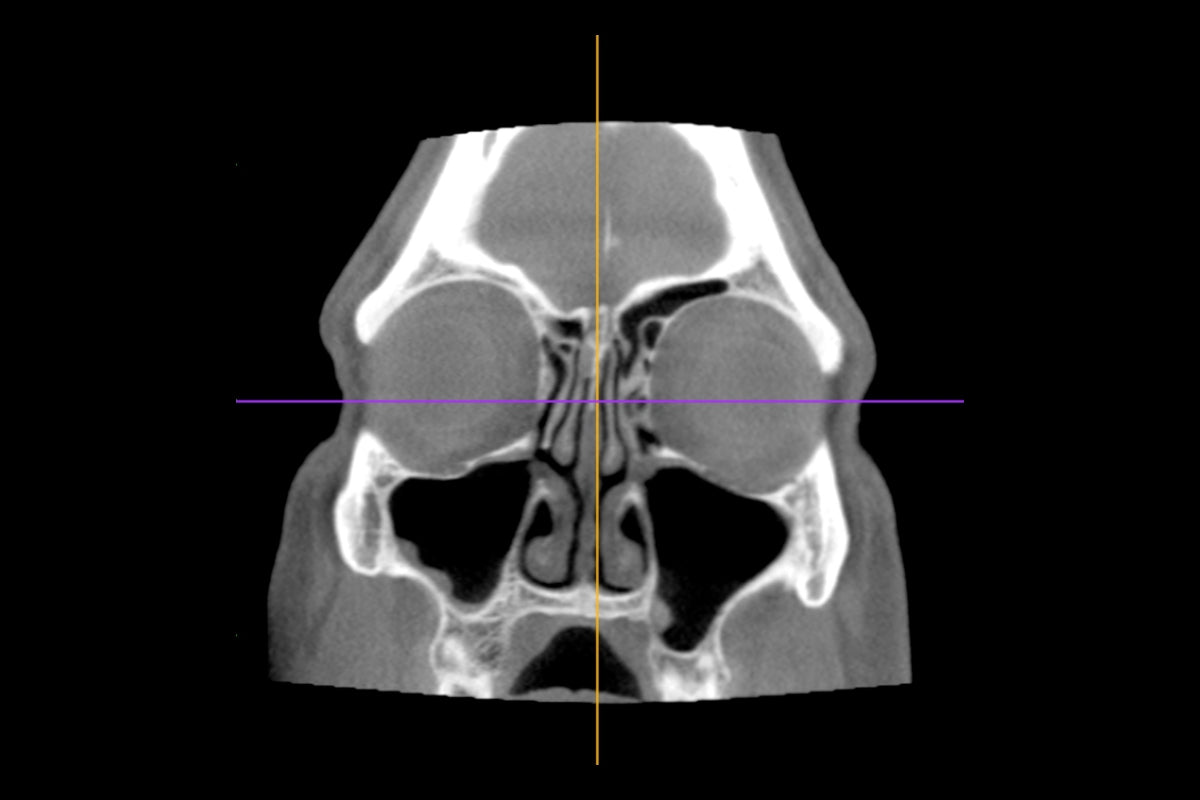

CT Scan

CT scan of sino-nasal cavities